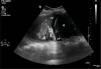

Presentamos dos casos de ecografía pulmonar, en dos pacientes ingresados en la UCI con insuficiencia respiratoria por SDRA, en ventilación mecánica de más de 7 días de evolución. En la figura 1, se aprecia el signo del «broncograma líquido» (flechas) consistente en imágenes lineales, ramificadas, que corresponden a bronquios distendidos rellenos de líquido y ausencia de aire, sobre parénquima pulmonar hipoecogénico, y que simulan un vaso sanguíneo, diferenciándose de estos por tener pared (hiperecogénica) y ausencia de señal doppler. Sugiere atelectasia pulmonar por obstrucción bronquial central. En la figura 2, vemos un parénquima pulmonar con punteado hiperecogénico, representando aire en el bronquio. Es el signo del «broncograma aéreo». En contexto clínico apropiado apunta a condensación pulmonar infecciosa (broncograma móvil) o atelectasia por compresión (broncograma fijo).